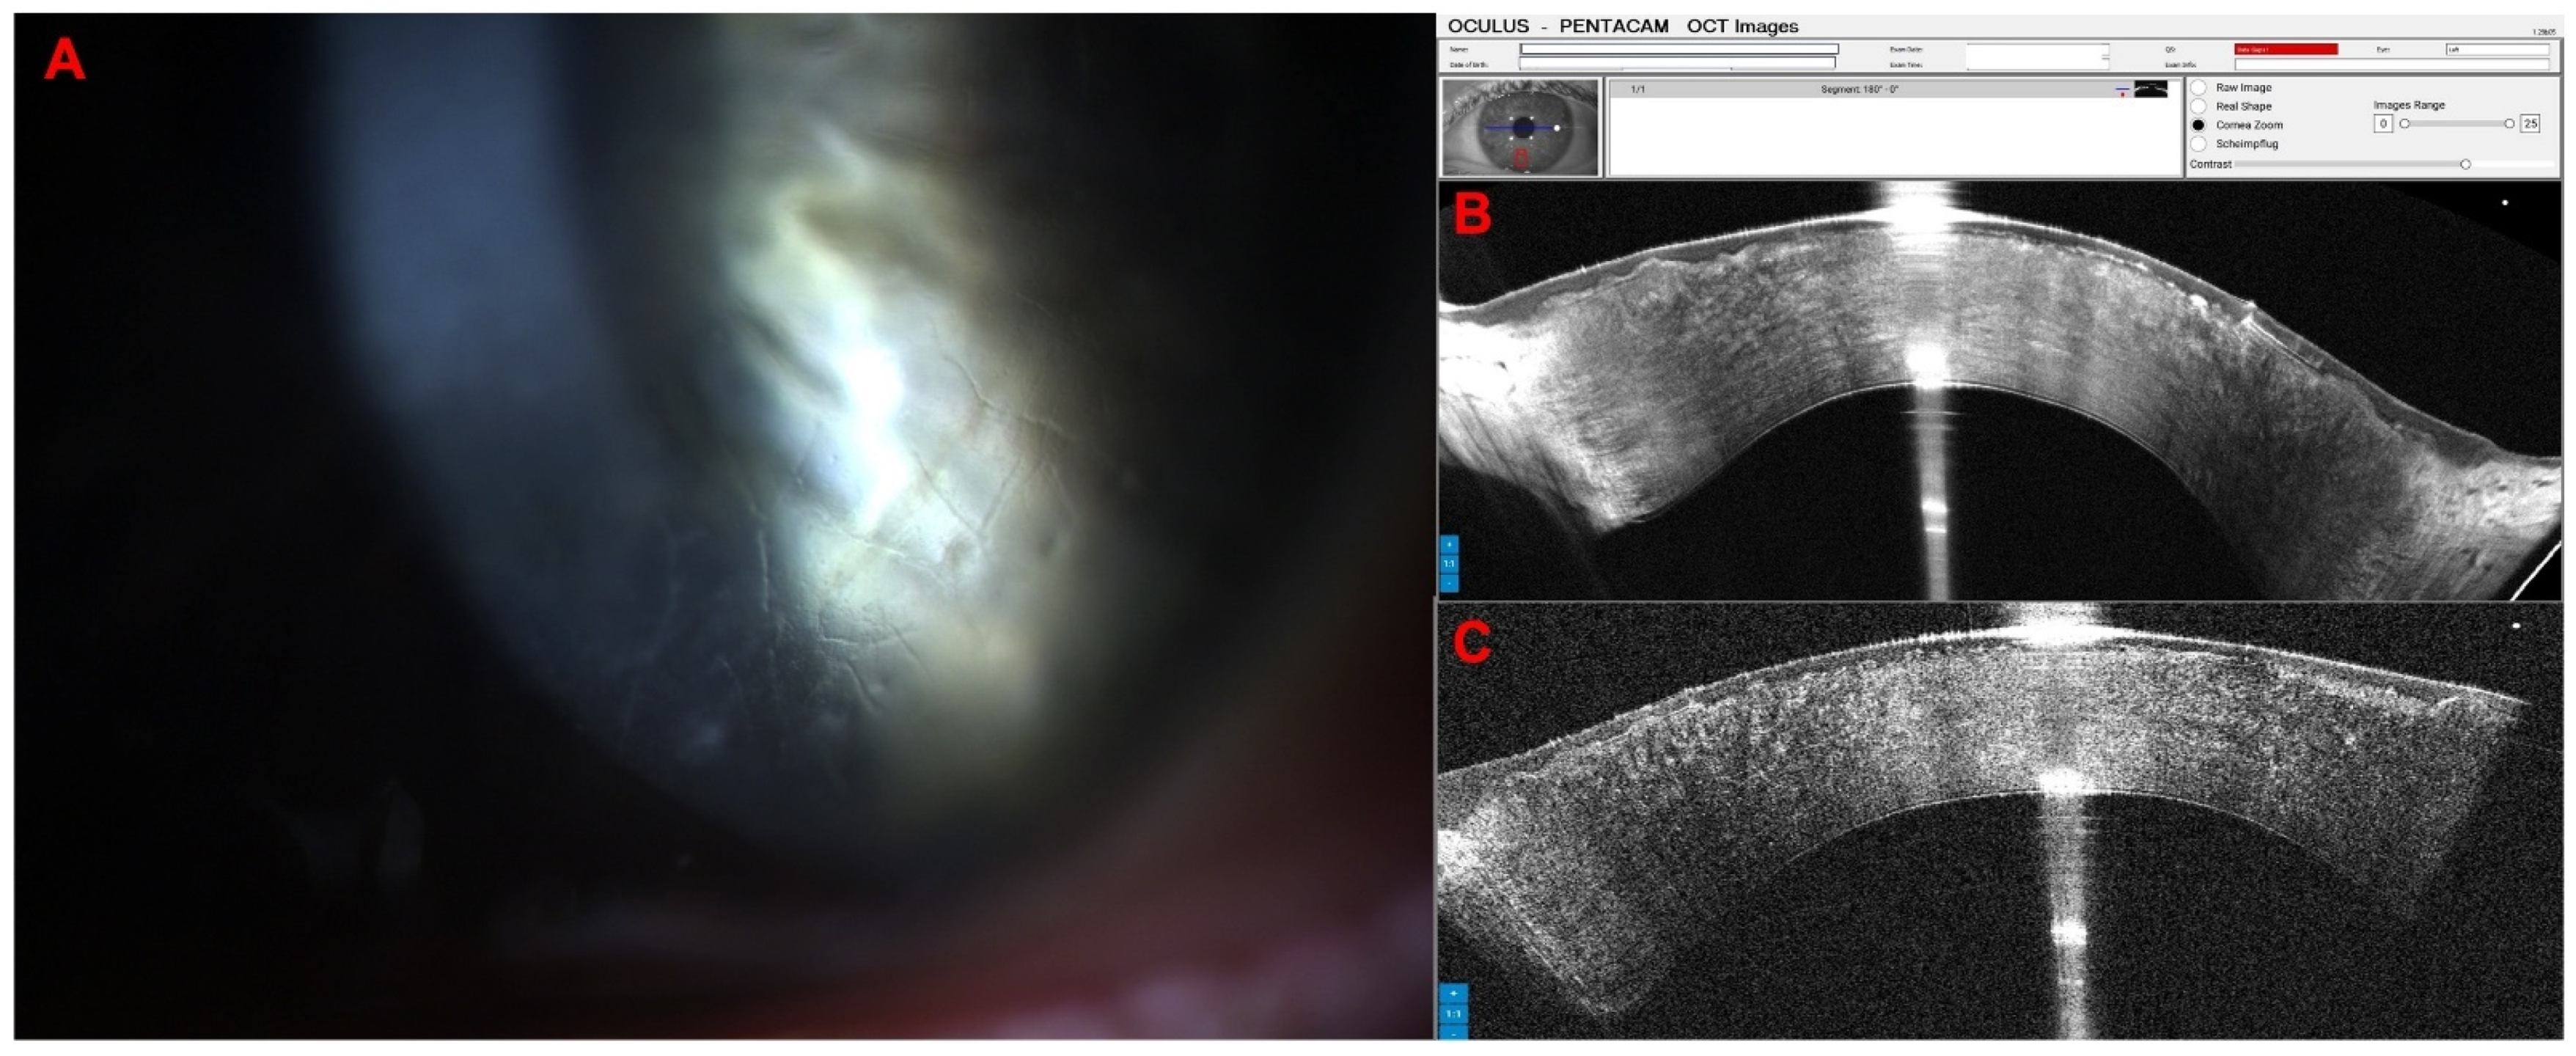

A 65-year-old female patient was diagnosed with Cogan dystrophy with uncorrected visual acuity (UCVA) of 20/30 in the right eye (OD) and 20/150 in the left eye (OS) and with distance-corrected visual acuity (DCVA) of 20/25 in the OD and 20/40 in the OS. Figure 3 shows the OS biomicroscopy with classical epithelium changes, and Figure 4 shows Pentacam OCT images (Scheimpflug, the actual shape of the cornea, and the cornea zoom, which corresponds to axial compaction) with abnormal epithelium layers.

Figure 4. Pentacam OCT showing Scheimpflug image (A), the real shape of the cornea (B), and the cornea zoom (C) demonstrating abnormal epithelium in Cogan dystrophy (same patient of Figure 3). In the Cornea Zoom view, the cornea’s thickness is stretched to visualize all fine anatomical details across the entire width in one image.